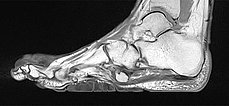

Präoperative Abklärung des Bindegewebsnävus in der MRT, hier sagittale T2-gewichtete, fettunterdrückte Sequenz des rechten Fußes. Der Bindegewebsnävus ist aufgrund des hohen fibrotischen Anteils homogen hypointens (schwarz).

Auch in der nativen, T1-gewichteten MRT sagittal ohne Kontrastmittel (gleiche Schnittebene) ist der Bindegewebsnävus homogen hypointens (schwarz).